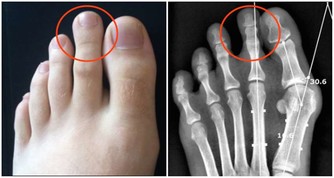

(12)關注身體異常變化

英國一項研究發現,在身體已出現異常症狀的患者中,提前3個月看醫生的人不足60%。早就醫、早診治是延長壽命的重要環節。

癌症就有一些徵兆,例如不明原因的體重驟減、高燒、極度疲勞、大小便習慣改變、異常出血、黑痣顏色和形狀異常、舌頭顏色異常等。